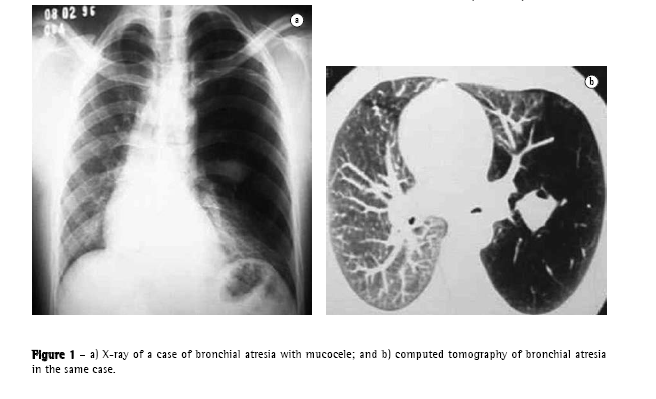

The yield of conventional chest X-ray in the evaluation of emphysema is quite limited. When there is no significant air trapping, the principal alteration is reduction of vasculature, which is only perceived too late in the natural history of the disease, and is an extremely subjective criterion. When there is air trapping (Figures 3 and 4), the criteria are safer, and can be divided into 3 basic groups of alterations,(6,8) presented in Chart 1. When all criteria are present, the diagnosis is definitively confirmed. It should be noted that the increased right chambers of the heart, with reduction of the intrasegmental vasculature, can also be identified in pulmonary arterial hypertension, without emphysema. It should also be noted that bullae are only present in approximately one-third of the cases.

The objectives of the radiological study of the chest in the evaluation of emphysema are diagnosis, identification of lesion type, and evaluation of the extent of the disease. In this sense, there have been studies(6,8) that called attention to some quite important considerations:

In centrilobular or paraseptal emphysema, there is typically no clinical symptomatology, and there can be increase in air spaces, without air trapping or clear radiological alterations; and

Although panlobular emphysema is typically more relevant in clinical terms, it can be present in the lungs of elderly individuals without causing air trapping.